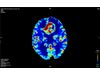

Cercare - Fully-Automated, Patient-Specific Perfusion Software for Brain CT and MRI

Cercare Perfusion is a fully-automated, patient-specific perfusion software for brain CT and MRI providing deep, fast, and reliable insights. We challenge current standards, so you can make confident assessments. Every time.

Cercare Perfusion provides high-quality parametric maps reflecting brain tissue microvascular integrity and function. No matter the circumstances we give you deeper and consistent insights needed to make confident assessments of brain CT and MRI.

Our technology accounts for capillary flow generating reliable parametric maps that do not only reflect the cerebral blood flow and the cerebral blood volume but provide additional information on brain tissue oxygenation with unique perfusion maps that have already proved to provide invaluable insights for the assessment of neurological disorders.